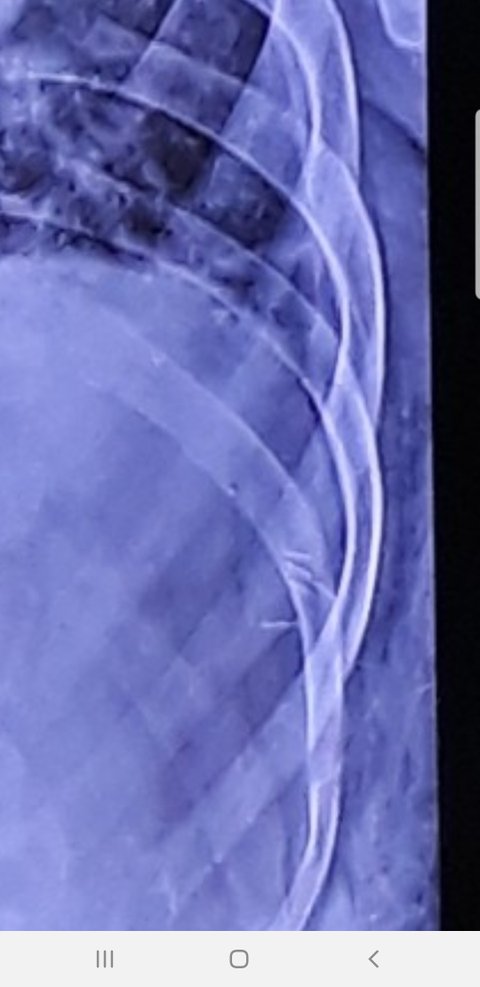

치료받았던 부위가 최근들어 더 시큼시큼해서 정형외과 가서 엑스레이를 찍었는데 이물질이

보인다 하여 CT까지 촬영한 결과

의사선생님이 혹시 최근에 한의원간적 있냐 물었다 하였고

지난달 교통사고로 한의원 4번 방문하여 침치료 받았다 했더니

지금 한의원에서 치료할때 사용하는 침 5개 (5개인지 안에서 조각이 5조각으로 난건지

수술해서 빼내야 알거 같다며 당장 제거 해야 한다는겁니다.(첨부해 드렸습니다.)